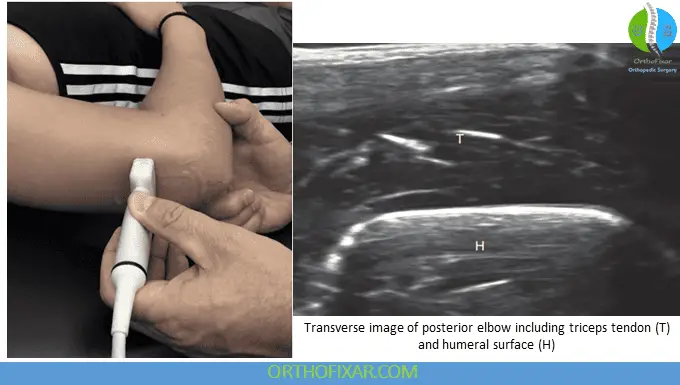

Triceps Tendon and Olecranon Bursa

The posterior elbow ultrasound examination visualizes the triceps tendon, anconeus muscle, and ulnar nerve. With the elbow flexed to 90 degrees and the arm resting on a table, the transducer is placed in short axis and moved from the olecranon process to the myotendinous junction. Careful probe manipulation may reveal the distinct medial, lateral, and deep components of the triceps tendon complex.

Triceps Tendon Characteristics

The triceps tendon demonstrates a fibrillar pattern similar to other tendons. Longitudinal examination, achieved by rotating the transducer 90 degrees, reveals the tendon as a linear structure with internal striations thought to represent fat between tendon fibers. Following the tendon distally shows its insertion over the olecranon and relationship to the olecranon fossa.